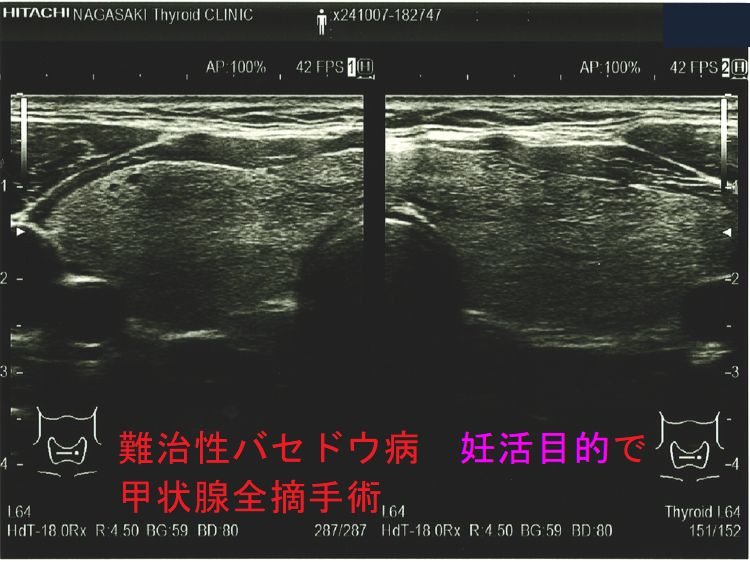

難治性バセドウ病 妊活目的で甲状腺全摘手術1

難治性バセドウ病 妊活目的で甲状腺全摘手術標本(矢状断)